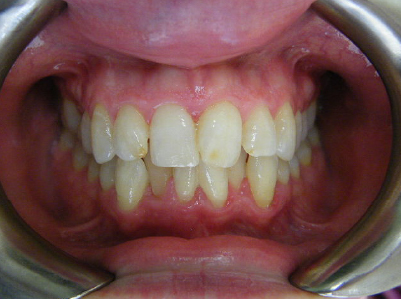

Patient 1: Severe upper and lower crowding with congenitally missing two lower adult teeth and a crossbite.